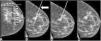

We included patients with histologically confirmed nonpalpable malignant lesions treated by surgery in 2015 or 2016. Patients were randomly assigned to presurgical marking with metallic clips (Group A) or with 125I seeds (Group B). In both groups, marking was guided by ultrasound and/or mammography depending on the radiologic characteristics of the lesion. During surgery, a gamma probe was used and afterward the presence of seeds in the surgical specimen was checked radiologically. In the histological analysis, the absence of tumour in the stain was considered free margins. We analysed the following variables: age, lesion characteristics (laterality, mean size on MRI and in the surgical specimen, radiological type), and presence/absence of free margins.

In Group A (n = 53), the most common histologic subtypes were infiltrating ductal carcinoma (IDC, 84.9%) and luminal A (LA, 49.1%); the mean size of the lesions was 1.8 cm. In Group B (n = 45), the most common histologic subtypes were IDC (82.2%) and LA (46.5%); the mean size of the lesions was 1.5 cm.

In Group A, 13.2% had involved margins and 13.2% underwent a second surgical intervention. In Group, B 11.4% had involved margins and 7.5% underwent a second surgical intervention. The differences between groups were not significant (p = 0.7 for involved margins and p = 0.5 for reintervention). The volume of the surgical specimens was significantly lower in Group B than in Group A (128.68 cm3 vs. 189.37 cm3; p < 0.05).